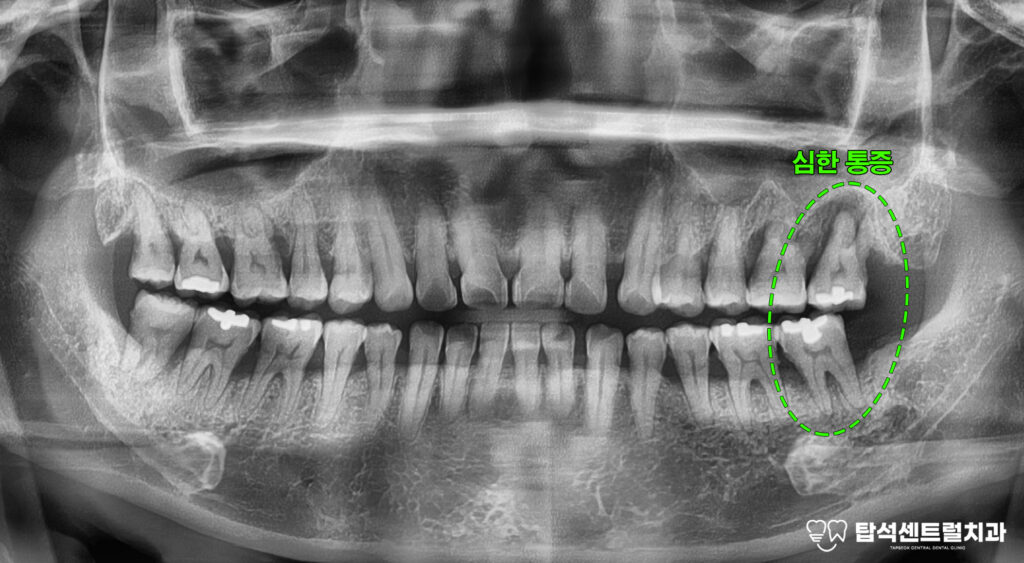

엑스레이 촬영을 통해 구강 상태를

확인하면 치주염으로 인한 전반적인

치조골 소실이 관찰되는 경우가 적지 않습니다.

치조골은 이를 지탱하는 뼈 조직으로

이 부분이 손상되면

치아 동요도가 증가하게 됩니다.

27번과 37번처럼

심한 동요도와 함께

통증을 호소하는 상황에서는

발치를 고려해야 되는 단계에

이르게 됩니다.